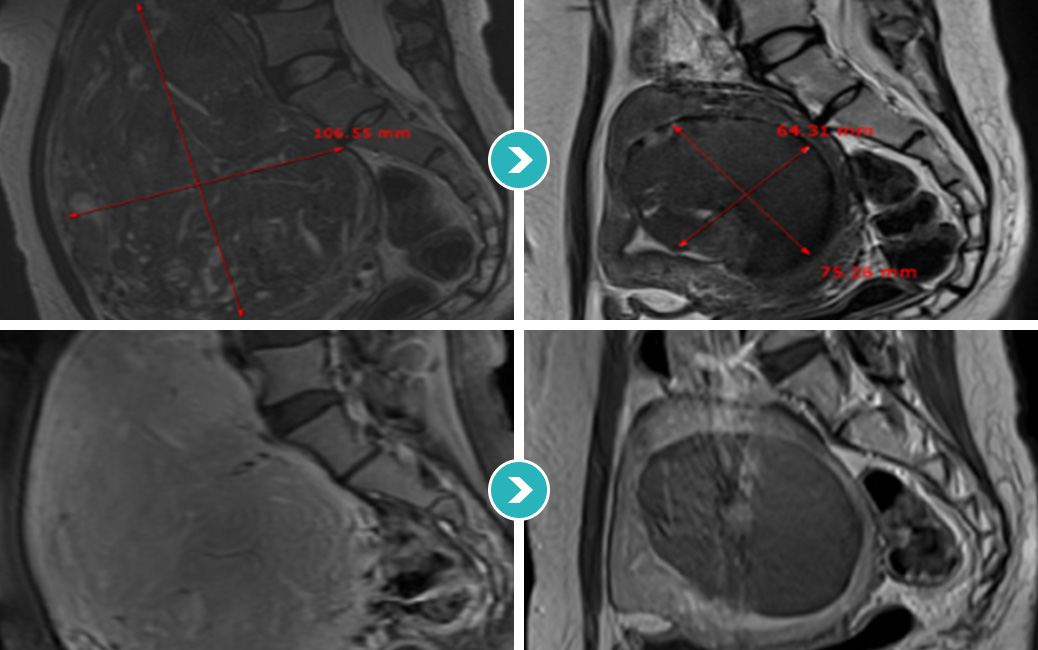

거대자궁근종(14Cm) 하이푸 치료18개월 장기간 추적관찰 STORY

2013년 11월 미혼여성 거대 자궁근종 관찰

질출혈과 생리과다 및 복부에만져지는 거대 자궁근종으로 자궁근종 하이푸 치료를 위해 내원하였습니다.

하이푸 시술전 MRI사진상 척추와 복벽을 밀고있는 14cm의 혈류가 풍부한 거대 자궁근종이 관찰됩니다. 자궁근종 하이푸 치료는 자궁근종 부위만 선택적으로

치료하는 시술로 자궁근종 전체적으로 자궁근종 하이푸 치료하였고, 14cm 거대 자궁근종 하이푸 치료시간은 164분이 소요되었습니다.

(Uterine Myoma Hifu treatment time 164min)

2014년 5월 거대 자궁근종 하이푸 시술 후 95% 이상 괴사

2015년 5월 자궁근종 하이푸 치료후 18개월 MRI 사진상 자궁근종의 부피 80.31% 감소